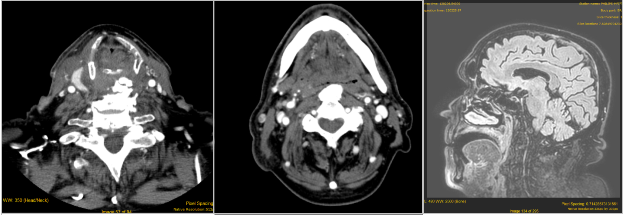

CERVICAL OSTEOPHYTES: A RARE CAUSE OF ACUTE DYSPNEA.

CERVICAL OSTEOPHYTES: A RARE CAUSE OF ACUTE DYSPNEA. Report of 2 cases with different evolution and li...